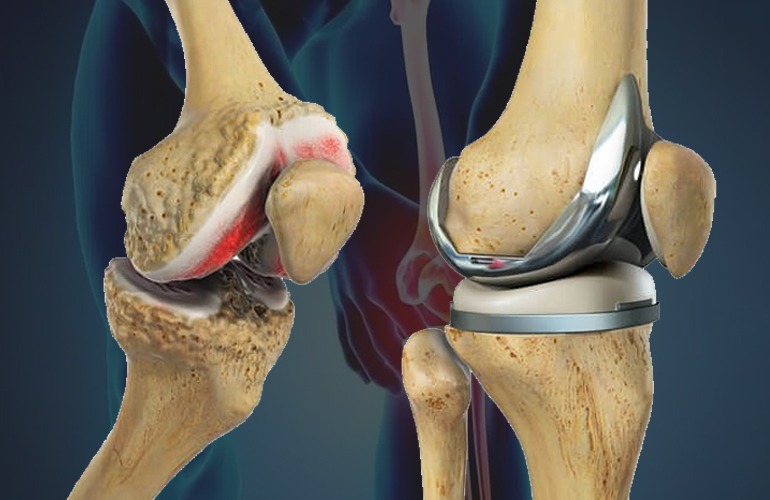

Which Are the Best Knee Replacement Options in South Bangalore?

Choosing a hospital for knee replacement surgery can feel overwhelming. With so many clinics and options, how do you know which one offers genuine care

HOW LONG DOES A KNEE REPLACEMENT REALLY LAST?

Are you planning to get knee replacement surgery and wondering about the outcome and how long it will last? Knee replacement is a major procedure,

Restore Mobility and Improving Quality with Joint Replacement Surgery

How important is joint replacement surgery when your daily life is disrupted by pain and limited movement? If you’re someone who’s been struggling to walk,

When Does Arthritis of Joint Need Surgery?

Did you know? Arthritis is one of the most common causes of disability globally. And when it hits your knees, it doesn’t just hurt, it